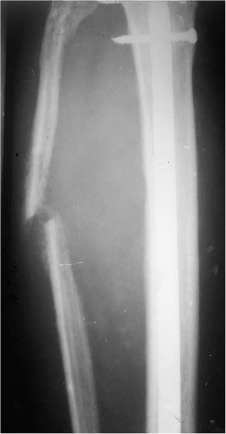

On the first presentation to our institute, physical examination revealed tender swelling with a gaping wound in the proximal half of the leg along with common peroneal nerve palsy. Dorsalis pedis pulse, although palpable, was feeble and reduced in volume as compared to the opposite side; posterior tibial pulses were normal though. Sequential roentograms which the patient had got done before coming to us, showed fracture tibia with intramedullary nail along with rarefaction and dissolution of fibula. A soft tissue swelling expanding laterally and pushing the fibula outwards and dissolving it in the process could be seen (Fig. 2 , Fig. 3  ;  Fig. 4 ).

Fig. 3

Fig. 3.

Radiograph done 4 weeks after primary surgery (nailing). Lateral expansion of the fibula erosion of the cortex seen on both tibia and fibula.